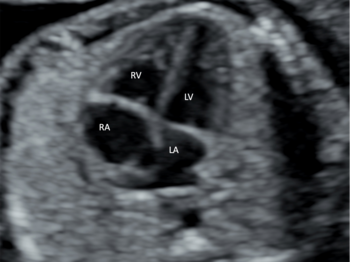

Zweit- und Dritt-Trimester-Screening zur Risikoabschätzung eines Herzfehlers

Mittels einer speziellen Feindiagnostik untersuchen wir in der Pränataldiagnostik und Schwangerenambulanz das Herz des Kindes genauer. Unter zusätzlichem Einsatz der (Farb-)Dopplertechnik können wir den Blutfluss direkt im Herzen, aber auch in den Gefäßen des Herzens messen.

Zahlreiche Herzfehler können so schon vorgeburtlich erkannt werden. Kinderkardiologinnen und Kinderkardiologen sowie Herzchirurginnen und Herzchirurgen können frühzeitig in die Beratung der Patientin eingebunden werden, sodass eine optimale Betreuung bei der Geburt gewährleistet ist. Eine frühe fetale Echokardiografie (spezielle Ultraschalluntersuchung des Herzens) kann im Rahmen der Erst-Trimester-Diagnostik zwischen der 12. und 14. SSW durchgeführt werden. Allerdings ist aufgrund der geringen Größe des Herzens die Zuverlässigkeit noch eingeschränkt. Wir empfehlen daher eine Kontrolle zwischen der 20. und 22. SSW.